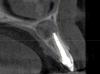

xo4ysoxranitzyb Опубликовано 28 октября, 2012 Поделиться Опубликовано 28 октября, 2012 Здравствуйте! Ситуация: зуб - верхняя левая двоечка, КИСТА.2009год: была огромная киста без формы. Три года терапевтически лечила, сейчас запломбировали канал, киста оформилась. Современный снимок прилагаю.Предлагают удаление зуба, я молодая, зуб передний, удалять не хочу.В ближайшем будующем планирую забеременеть - пугают возможным воспалением кисты.Вопрос:1. поможет ли резекция верхушки корня (с учетом размера кисты)2. что будет, если ничего не делать (не удалять зуб, не делать резекцию). Может ли киста сама исчезнуть?3. как поступить с кистой(зубом) с учетом будущей беременности (потом нельзя антибиотики, анастезию и т.п.) -----у меня 3Д снимок, если требуется приложу любой вид Ссылка на комментарий